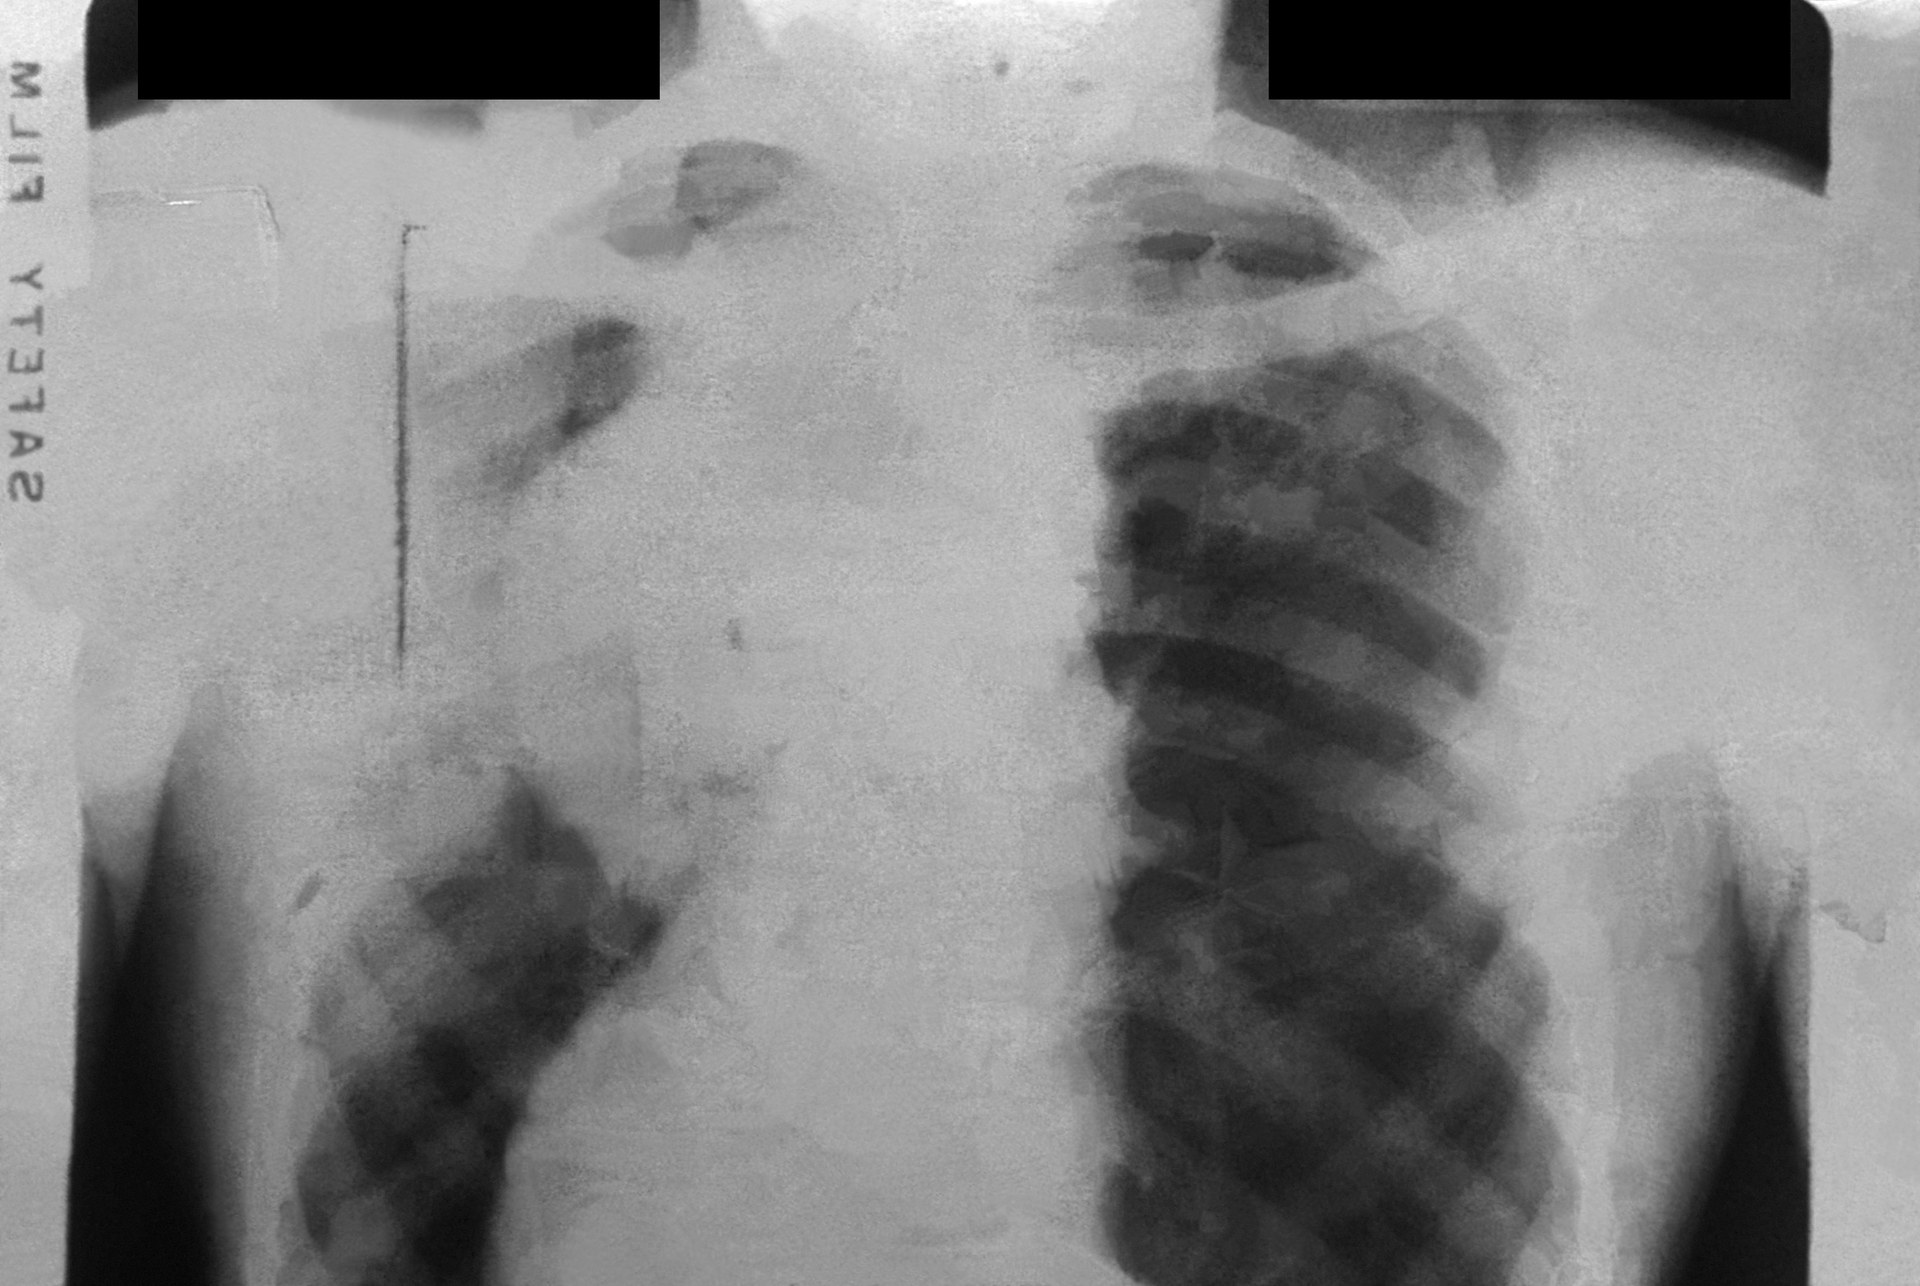

The research, which is published in Nature Genetics, relied on data from the UK Biobank, a study that performed multiple magnetic resonance imaging tests of the heart and aorta in more than 40,000 people. “There were no aortic measurements provided by the UK Biobank, and we wanted to read the aortic diameter in all of the images collected,” explains lead author James Pirruccello, MD, Cardiologist at MGH and Instructor in Medicine at Harvard Medical School. “That is very hard for a human to do because it would take a long time, which motivated our use of deep learning models to do this process at a large scale.”

The researchers trained deep learning models to evaluate the dimensions of the ascending and descending sections of the aorta in 4.6 million cardiac images. They then analyzed the study participants’ genes to identify variations in 82 genetic regions (or loci) linked to the diameter of the ascending aorta and 47 linked to the diameter of the descending aorta. Some of the loci were near genes with known associations with aortic disease.